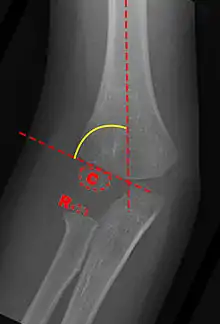

Anterior X-ray

Carrying angle can be evaluated through AP view of the elbow by looking at the Baumann’s angle.[2] There are two definitions of Bowmann's angle:

The first definition of Baumann's angle is an angle between a line parallel to the longitudinal axis of the humeral shaft and a line drawn along the lateral epicondyle. The normal range is 70-75 degrees. Every 5 degrees change in Bowmann's angle can lead to 2 degrees change in carrying angle.[5]

Another definition of Baumann's angle is also known as the humeral-capitellar angle. It is the angle between the line perpendicular to the long axis of the humerus and the growth plate of the lateral condyle. Reported normal values for Baumann's angle range between 9 and 26°.[6] An angle of more than 10° is regarded as acceptable.[6]